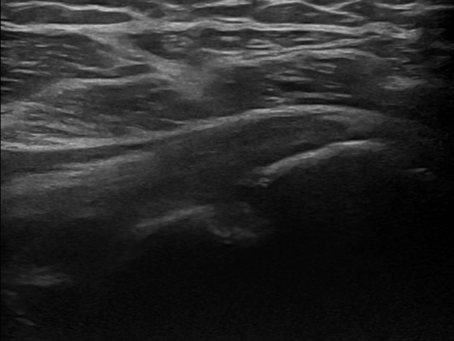

This e-learning platform has been developed by SonoPedics as a teaching and educational resource for clinicians and musculoskeletal practitioners. The platform comprises a large number of neuromusculoskeletal ultrasound cases, which have been collected over the years in clinical practice at hospital settings.

The ultrasound cases comprise images of the pathology and a detailed description of the sonographic findings. Video loops and/or images of other imaging modalities, like MRI and X-ray, are also added, if applicable.